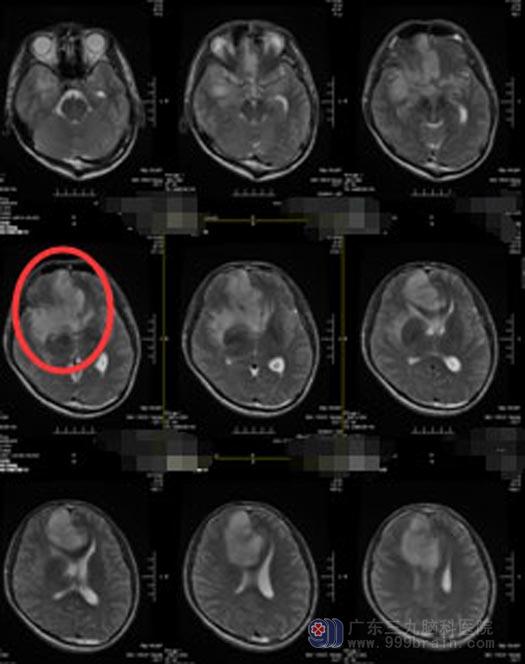

进一步MRI检查显示:右额颞岛叶-左侧额颞叶见不均匀异常信号影,大小约为65mm×45mm×71mm,边界模糊,诊断:.右额颞岛叶-左侧额颞叶弥漫性占位性病变,考虑高级别胶质瘤,以间变性星形细胞瘤可能性大。